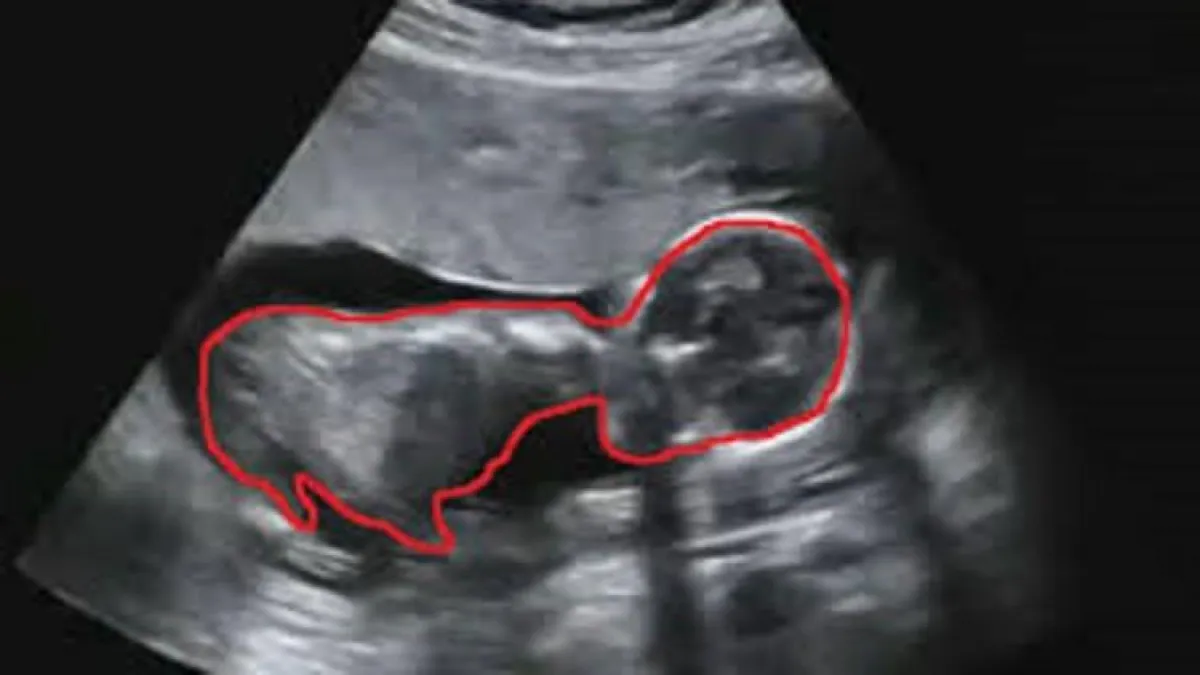

وكان الطبيب المتابع لحالة أم الطفل، بيتان سيمبثون، من مدينة برينهام، اكتشف أثناء الفحص بالموجات الصوتية للأم في الشهر الخامس من حملها وجود تشوّه في الجنين، أثبتته الفحوص اللاحقة، وأكّدت أن الجنين مصاب بتشقق "الصلب الأشرم"، وهو ما يسبب نمواً غير كاملاً للحبل الشوكي.